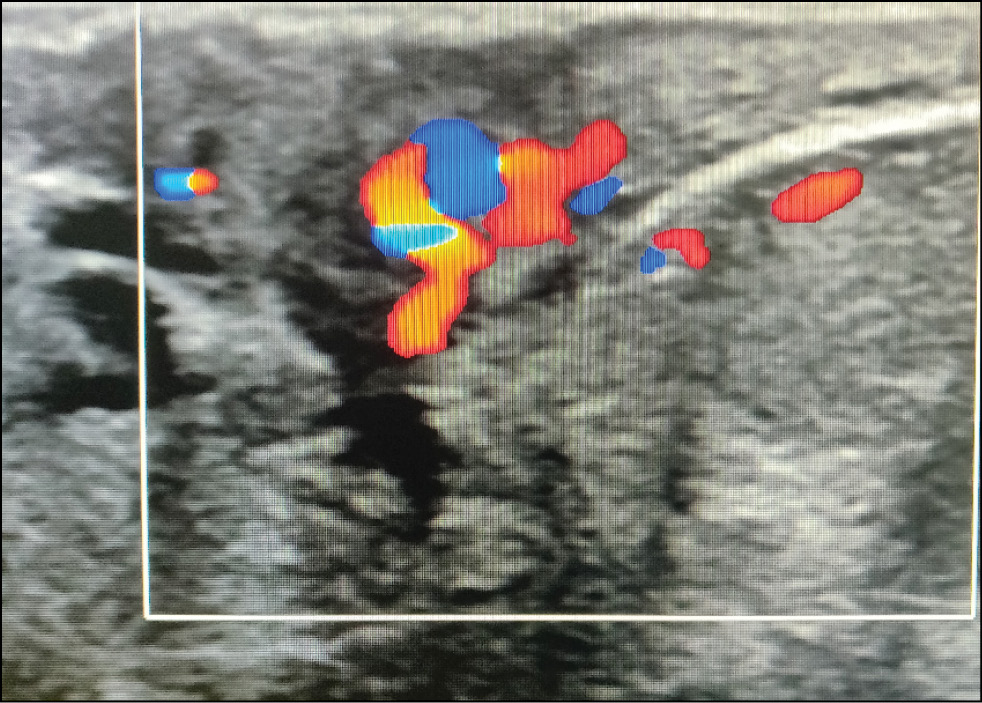

A 59-year-old patient complained of erosive changes in the nipple (Fig. 1). Physical examination revealed erythema, erosion, and nipple retraction. Doppler ultrasonography with color flow mapping revealed increased blood flow in the nipple projection (Fig. 2). Mammography findings were normal. To assess the extent of disease spread, breast MRI with contrast enhancement was performed. The early postcontrast series (Fig. 3) and maximum intensity projection (MIP) images (Fig. 4) showed a segmental contrast retroareolar area from the nipple level to posterior breast sections. Ultrasound-guided core biopsy followed by immunohistochemical analysis revealed Paget’s disease of the nipple with high-grade intraductal carcinoma in situ. Receptors for estrogen (G3 ER) and progesterone (PR) were negative. Oncogenic protein Ki-67 was 45%.

Figure 2. Paget’s disease: increased blood flow on color Doppler imaging.

Imaging techniques are of critical importance because in 90% of cases, Paget’s disease is associated with ductal carcinoma in situ or invasive cancer. [13, 20] In primary mammography, images with enlarged NAC and anterior breast third are important. Skin thickening, retroareolar masses, or pleomorphic microcalcifications may be detected. Ultrasonography showed no characteristic signs. It may help identify dilated subareolar ducts, calcifications, and nipple changes.